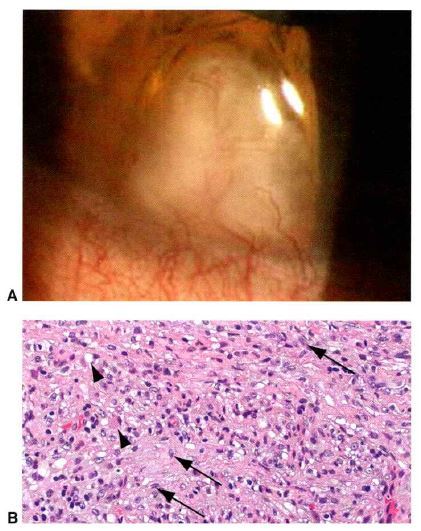

Q

What is this condition? And what does scleral biopsy illustrated?

A

Necrotizing granulomatous scleritis and palisading arrangement of histiocytes and multinucleated giant cells.